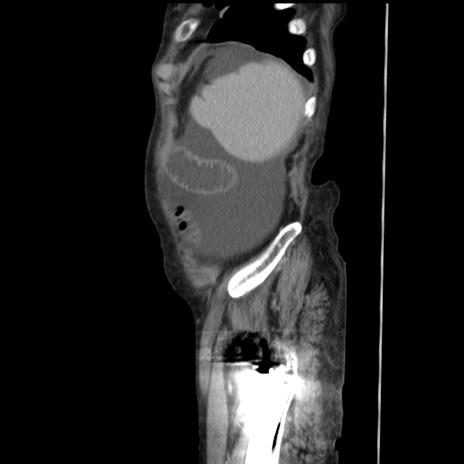

症例31(矢状断像)

【症例】80歳代 女性

【主訴】腹部膨満感

【現病歴】他院にて肝硬変にてフォロー中。1週間前から便秘、腹部膨満感、臍部腫瘤あり受診となる。

【既往歴】肝硬変

【身体所見】腹部膨隆あり、皮膚変化なし、疼痛なし。

【データ】WBC 4600、CRP 0.25